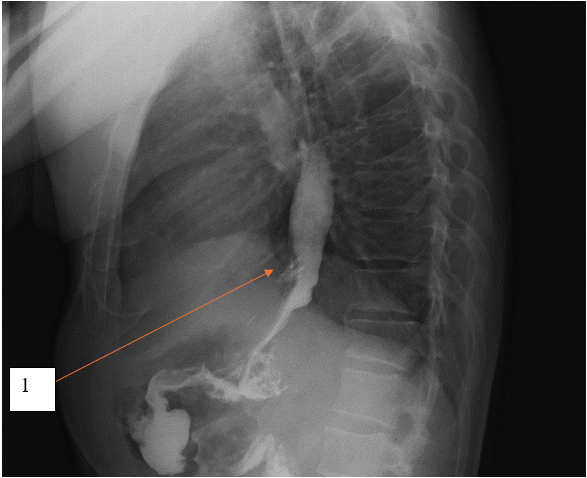

По данным компьютерной томографии органов брюшной полости с внутривенным контрастированием выявлена структура жидкостной плотности в области кардиального отдела желудка без убедительной связи с просветом желудка. Единичные увеличенные параэзофагельные, паракавальные, парааортальные лимфоузлы. Другой патологии не выявлено. Результаты компьютерной томографии с внутривенным контрастированием представлены на рисунках 1 и 2.

Рис. 1. Компьютерная томограмма с внутривенным контрастным усилением, пациент К., 54 года, фронтальный срез, отсроченная фаза. 1 – структура жидкостной плотности в области кардиального отдела желудка

Fig. 1. Computed tomogram with intravenous contrast enhancement, patient K., 54 years old, frontal section, delayed phase. 1 – liquid density structure in the cardiac region of the stomach